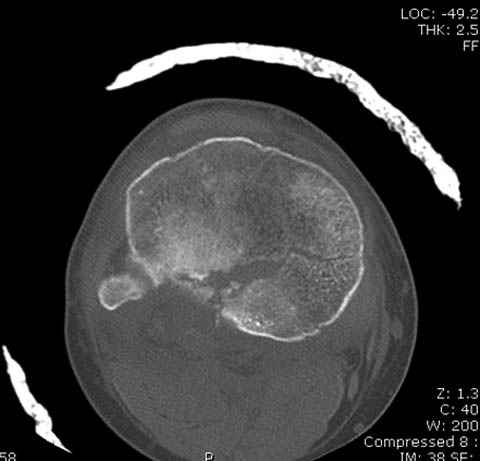

Здесь как раз тот случай, когда результат зависит не только от мастерства хирурга, но и от наличия современных методов исследования. Например, КТ которая поможет рассчитать направления шурупов и установку импланта. Кроме этого, поможет определиться с доступом.

На представленных предоперационных срезах КТ огромный задне-медиальный фрагмент расположен больше кзади, чем медиально. Для планирования, кроме поперечных срезов, надо ориентироваться на корональные срезы, которые укажут топографию верхушки медиального фрагмента.

При сложных переломах тибиал плато для своего рода Damage Control мы иногда применяем поэтапную тактику. Сперва оперируется одна сторона, а потом после рекондиции мягких тканей окончательный этап.

Если состояние мягких тканей позволяет, я бы предложил такой метод для вашего больного. Без предварительного планирования будет трудно, но шанс не надо упускать. Всего несколько дней после операции, и такая тактика лучше, чем недовольный молодой пациент.